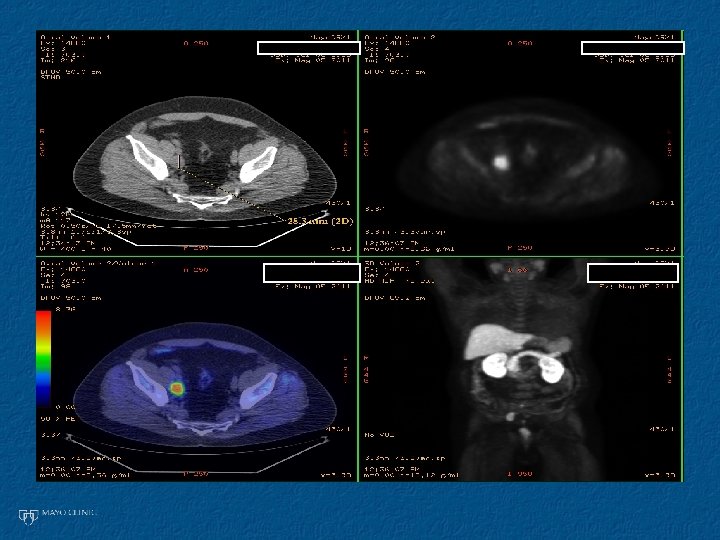

65 yo GS 7 PSA <10 2006: RP p. T 2 c. N 0 R 0 Salvage XRT 0. 4 then steady climb PSA 1. 7 2008: s. LND Currently PSA <0. 2 without ADT 1 st EPLND post RP/PLND w PET